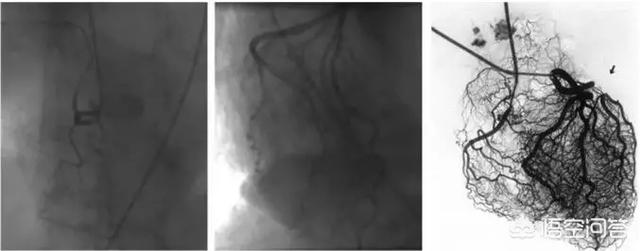

1.微小血管病変

冠動脈造影が正常であっても、心筋虚血が全くないとは言えない患者もいることは認めなければならない。というのも、人間の目は直径0.4-0.5mm以上の太い血管の狭窄や病変の存在しか見ることができず、前方小動脈、細動脈、毛細血管などの微小血管は冠動脈造影だけでは評価できないからである。胸が締め付けられるような症状があり、心筋虚血の証拠があるにもかかわらず、冠動脈造影が正常である人がいるのはこのためである。

2.冠微小血管疾患。冠微小血管疾患(CMVD)とは、様々な病原因子の影響下にある前部小冠動脈および小動脈の構造的および/または機能的異常によって引き起こされる労作性狭心症または心筋虚血の客観的証拠の臨床的症候群を指す。冠動脈には前部小動脈(直径0.1~0.5mm)、細動脈(直径0.1mm未満)、心外膜下冠動脈(直径0.5~5mm)の3つの部分がある。 冠動脈細動脈には前部小動脈と細動脈が含まれ、その構造的・機能的異常も狭心症やその他の臨床症状を引き起こす。

冠動脈造影検査では、大血管の問題は検出されるが、冠動脈小血管の問題や、微小循環が存在する微小循環けいれんは検出されない傾向がある。多くの場合、冠動脈造影では問題を発見する方法はない。

この種の患者の冠動脈造影画像を注意深く見ると、この種の人の血流は比較的遅いことがわかる。 正常な人に造影剤を注入した後、冠動脈は心臓の1、2回の拍動ですぐに満たされるが、血流の遅い患者の冠動脈は心臓の3、4回の拍動、あるいは5、6回の拍動で満たされる必要がある。 冠動脈の充血が遅いため、正常な血液の排出が心筋の必要量を満たすことができず、心臓の前部に不快感が生じる。

まず第一に、画像診断では心臓の太い血管と太い枝を見て、微小循環は見ることができない。心臓の微小循環が悪いために胸が締め付けられるような症状を繰り返す人もいるが、心臓の微小循環障害は血管の内皮機能の低下に関係している可能性がある。例えば、長年の喫煙、長年の糖尿病、高血圧などが心臓の微小循環障害を引き起こす可能性がある。